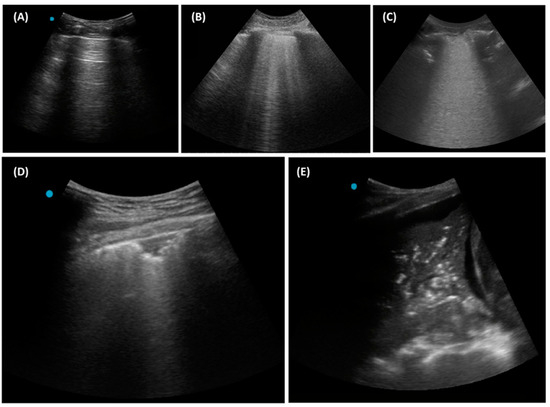

3.1. Essential Lung Ultrasound Patterns